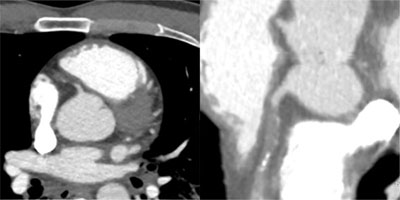

A 12-lead ECG (Figure 2) demonstrates an acute myocardial infarction. An urgent angiography was performed (Figure 3). The angiography shows a complete occlusion of the right coronary artery (RCA), probably due to a traumatic dissection. Multiple stents were placed to approve reflow of the myocardium. There was no reflow to the myocardial tissue established, and the patient, unfortunately passed away. On review of the trauma CT, the dissection of the RCA was visualized (Figure 4).

Figure 4

Spiral acquisition trauma CT of the thorax and abdomen after intravenous injection of 100 ml iodized contrast. Focus on the heart showing dissection and complete occlusion of the RCA. Left image: axial view, right image: curved view.

In this case report, the patient first underwent a non-ECG gated full body trauma CT where at first the coronary dissection was not seen. After diagnosis of the myocardial infarction with ECG and proven dissection/occlusion of the RCA on coronary angiography we reviewed the CT. In retrospective, the coronary artery dissection was revealed. We found no case reports where a coronary dissection was observed on non-ECG-gated trauma CT. Faster and wide detector CT technology makes trauma CT an imaging tool for detection of coronary dissection even if the scan is non-ECG gated. Especially patients with a slow heart rhythm or bradycardia have a much higher potential for detection of the dissection/occlusion of the coronaries. Radiologists and clinicians should be aware of this and look more peculiar to the coronary arteries when assessing a trauma CT of the chest.